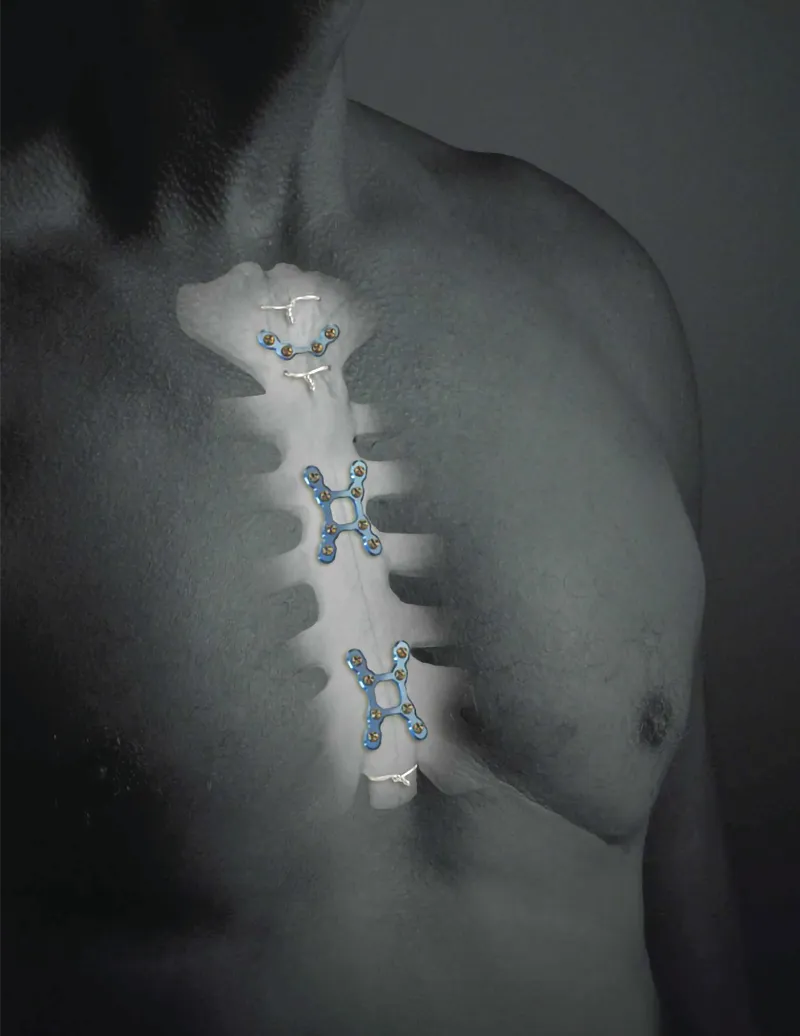

RIBFIX BLU

Cerrando la brecha en fijación rígida. RibFix Blu ™ es un sistema integral de fijación torácica que permite ...